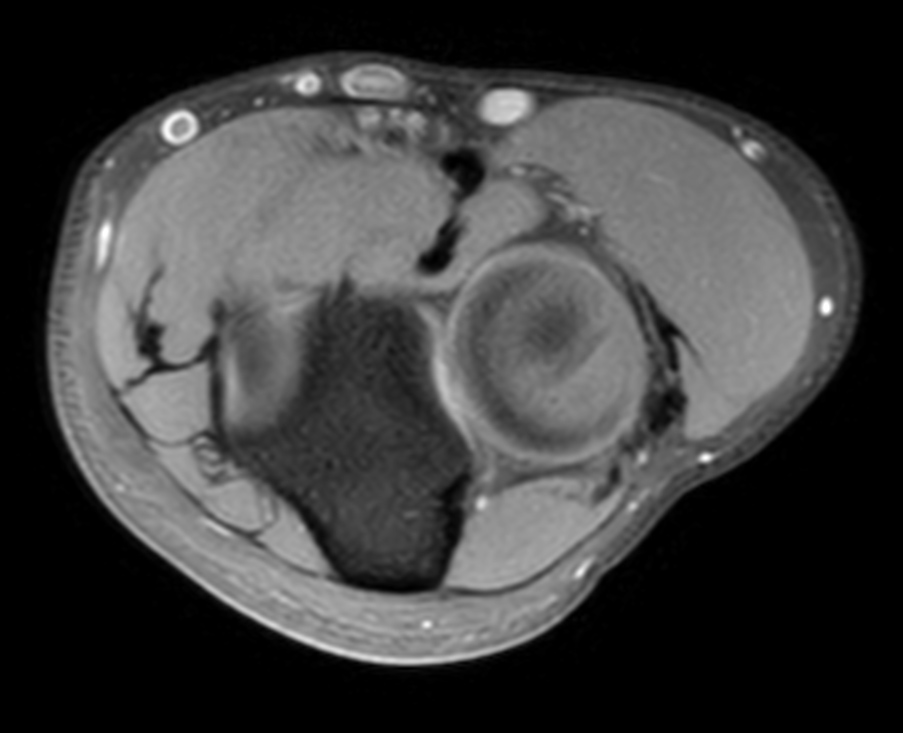

High quality Elbow imaging with Compressed SENSE

Spital Uster, Switzerland